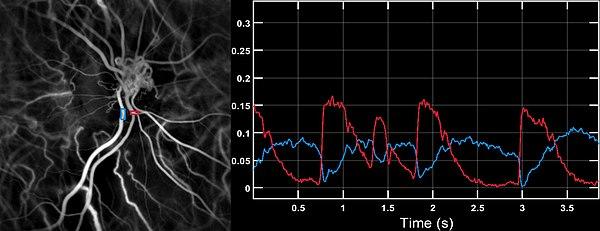

Premature heart beats can be asymptomatic (the patient does not complain about anything). The subject may experience palpitations, a feeling of cardiac "pause". Taking (prolonged) pulse may result in a rhythm that seems irregular. Electrocardiography and laser Doppler imaging[2] allow to visualize Premature heart beats. From their appearance, their location can be assessed. The Holter monitor allows to quantify them, to specify their characteristics and their repetition.

- ^ Puyo L, Paques M, Fink M, Sahel JA, Atlan M (October 2019). "Waveform analysis of human retinal and choroidal blood flow with laser Doppler holography". Biomedical Optics Express. 10 (10): 4942–4963. doi:10.1364/BOE.10.004942. PMC 6788604. PMID 31646021.